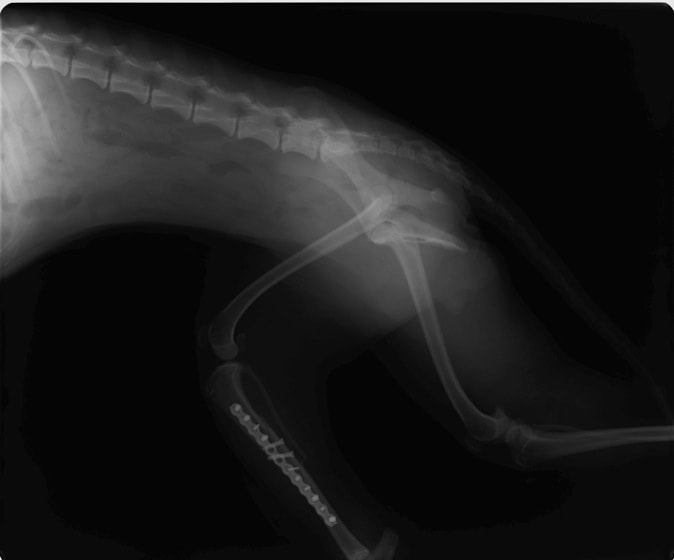

症例3:キルシュナーワイヤーのピンニングによる整復

ペルシャ猫 11ヶ月齢 雄

他院にて左大腿骨遠位の成長板骨折(salter-harrisⅠ型)が認められており、治療相談を目的として来院。当院にて、キルシュナーワイヤーを用いたピンニングにより骨折部位の整復を行いました。術後の経過は良好で、現在も経過観察中です。

術前レントゲン

術後レントゲン